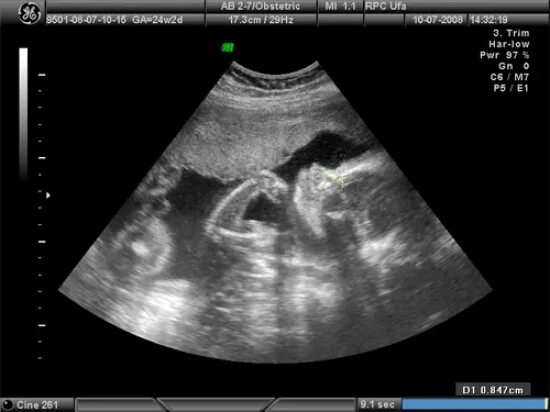

Узи 6 месяцев